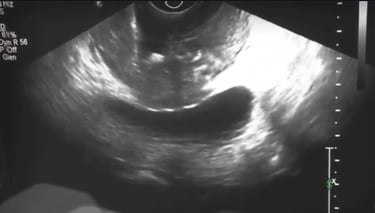

Transrektal Yöntem: En sık kullanılan yöntemdir. Ultrason probu rektuma yerleştirilir ve biyopsi iğnesiyle prostat dokusundan örnek alınır.